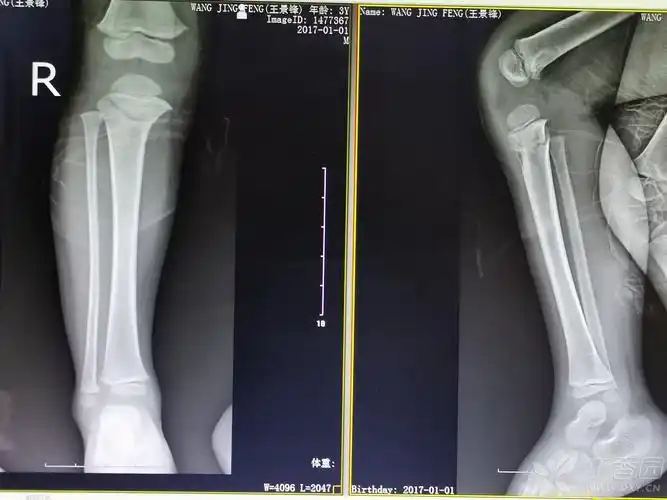

儿童胫骨近端骨折的非手术治疗.